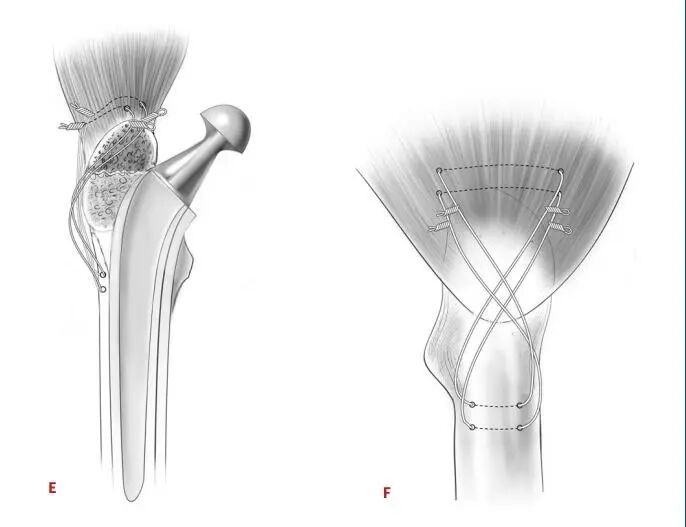

图2:说明大转子张力带钢丝固定技术图。A和B:髋关节正位和侧位,显示两根钢丝穿过股骨外侧皮质的钻孔,位于溶骨性病变下方远端,上方大粗隆尖端,呈八字形。C和D:髋关节正位和侧位,显示8字形钢丝在扭转前的位置,而助手使用复位钳将大转子的碎片重新接近股骨近端。E和F:髋关节正位和侧位,显示用颗粒状同种异体骨填充缺损处并用钢丝紧紧缠绕后,大转子重新附着。

图4:A和B图示大转子斜向环扎钢丝固定图。髋关节正位图(A)和侧位图(B)显示一根金属丝绕过大转子和小转子,用于固定大转子骨折并大转子和小转子骨溶解,然后用颗粒状同种异体骨移植充分填充溶骨病变。